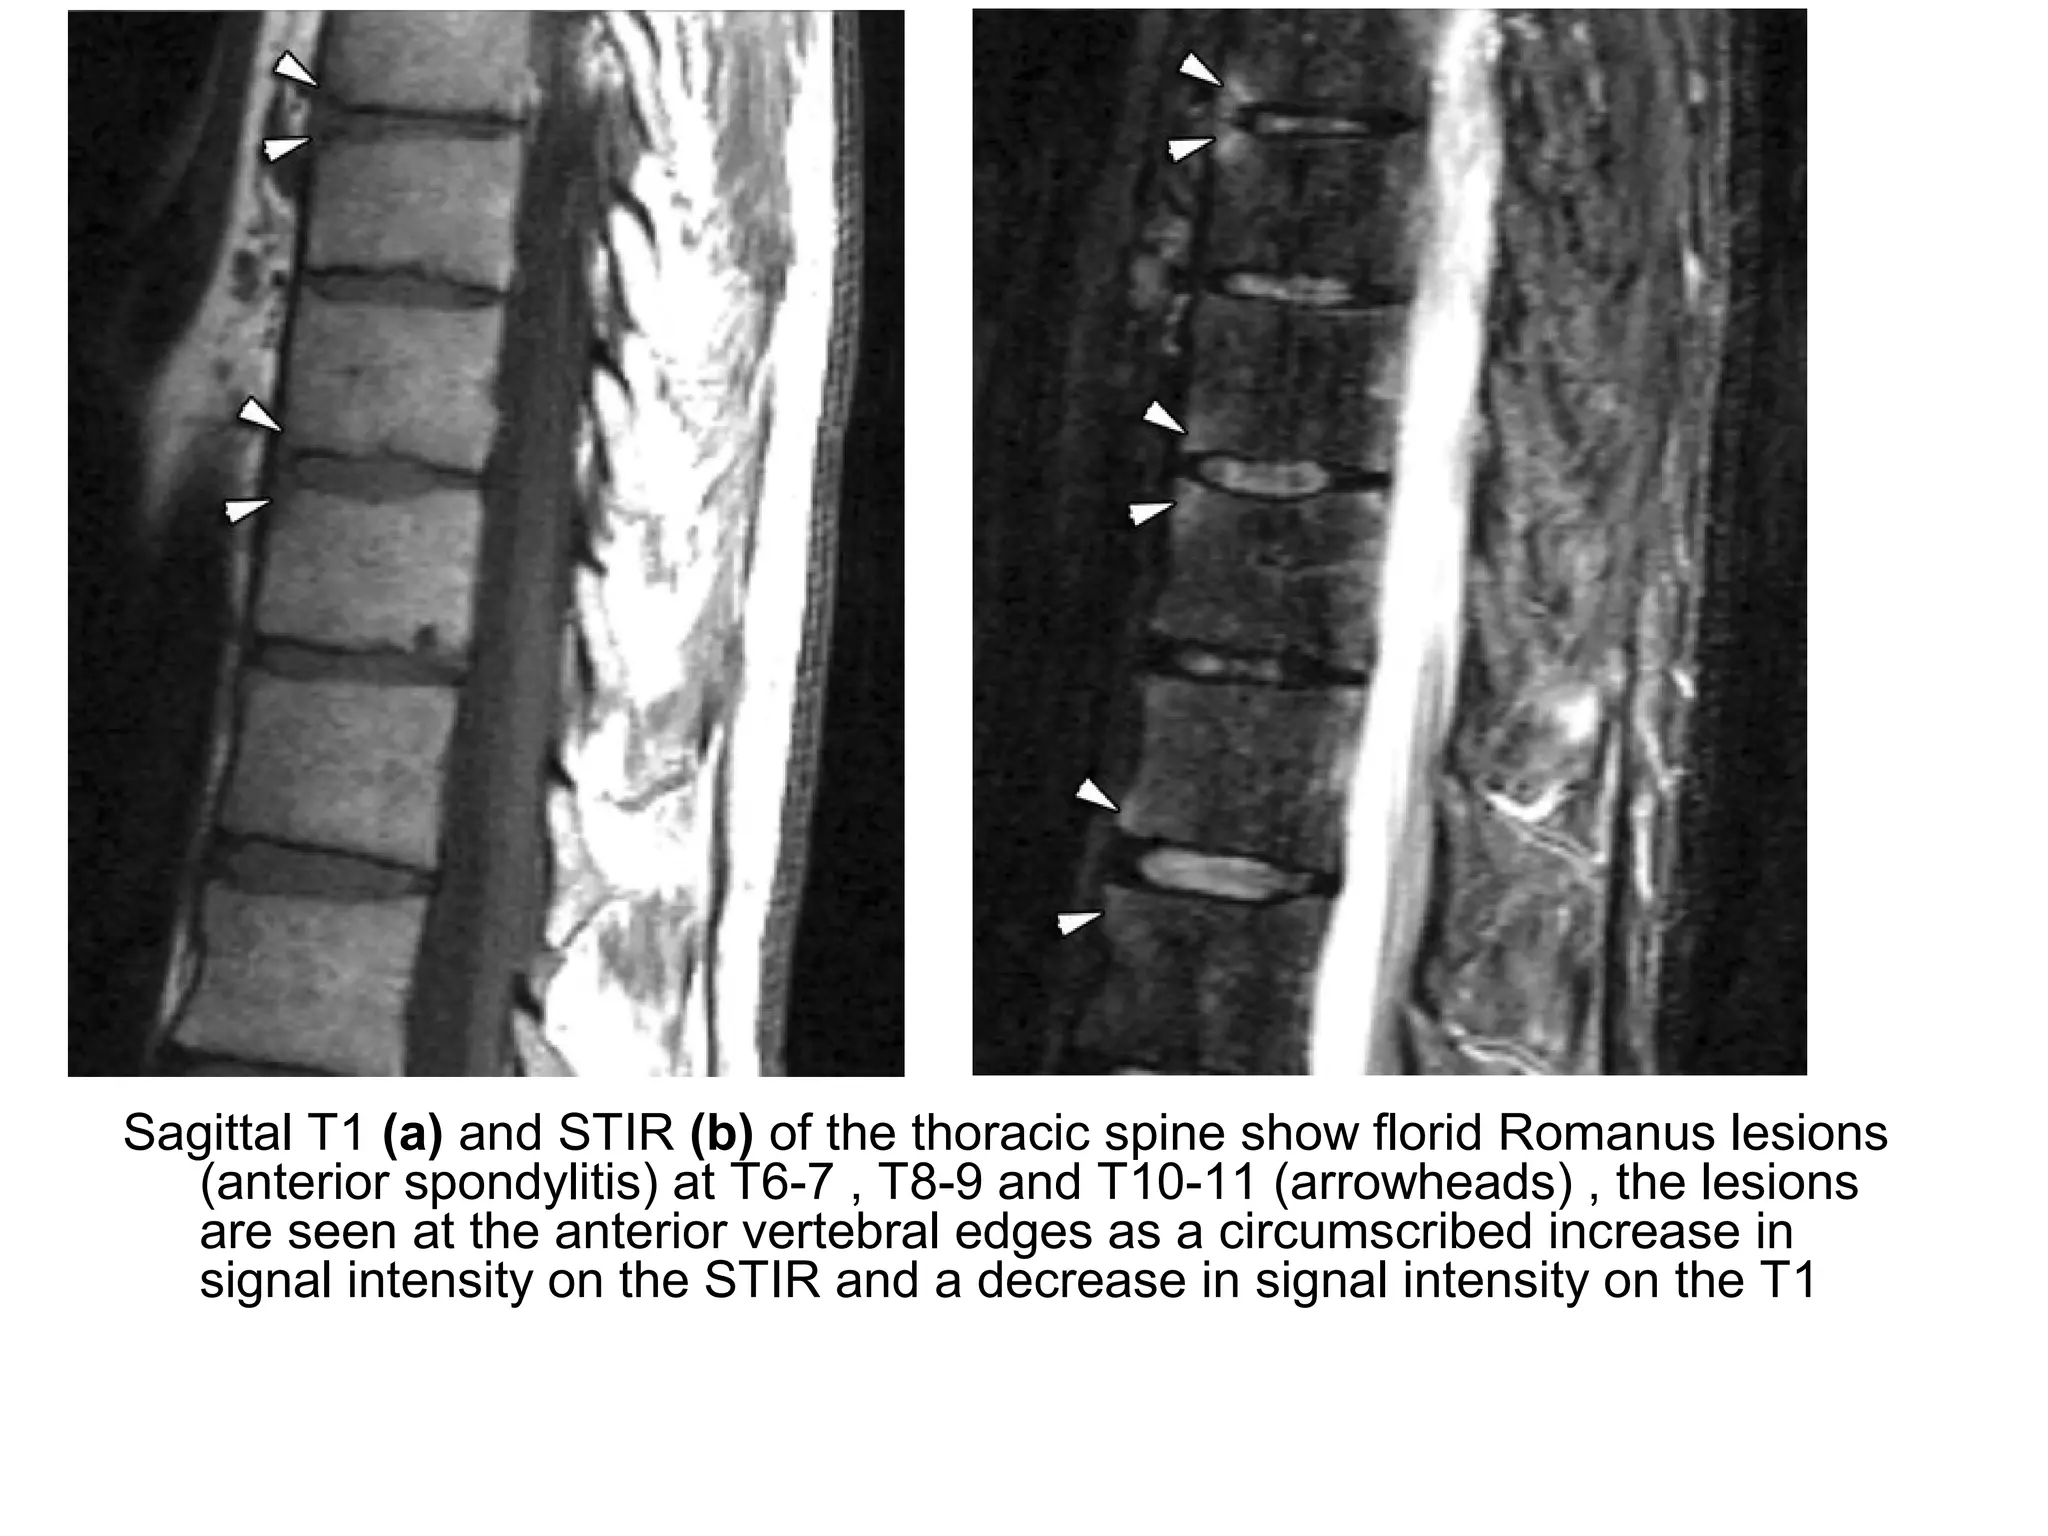

1- Romanus Spondylitis :

-Consists of inflammatory changes involving the

edges of the vertebral endplates

-Involvement of the anterior edges is secondary to

enthesitis of the anterior longitudinal ligament

whereas involvement of the posterior edges is

secondary to enthesitis of the posterior

longitudinal ligament

-Hyperintense edematous corners on T2 and T1+C

fat-suppressed , low signal in T1

Sagittal T1 (a) and STIR (b) of the thoracic spine show florid Romanus lesions

(anterior spondylitis) at T6-7 , T8-9 and T10-11 (arrowheads) , the lesions

are seen at the anterior vertebral edges as a circumscribed increase in

signal intensity on the STIR and a decrease in signal intensity on the T1